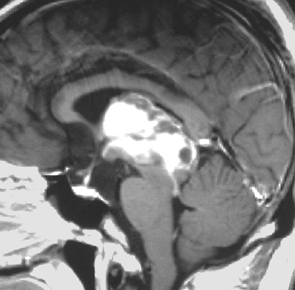

成人男性が早朝の頭痛で発症しました。閉塞性水頭症になっているので第3脳室開窓術が行なわれてから紹介されてきました。開頭手術で全摘出して,病理が PPTID グレード3でしたので,脳脊髄照射 24Gy/12fr と腫瘍局所照射 54Gy/27fr をしました。